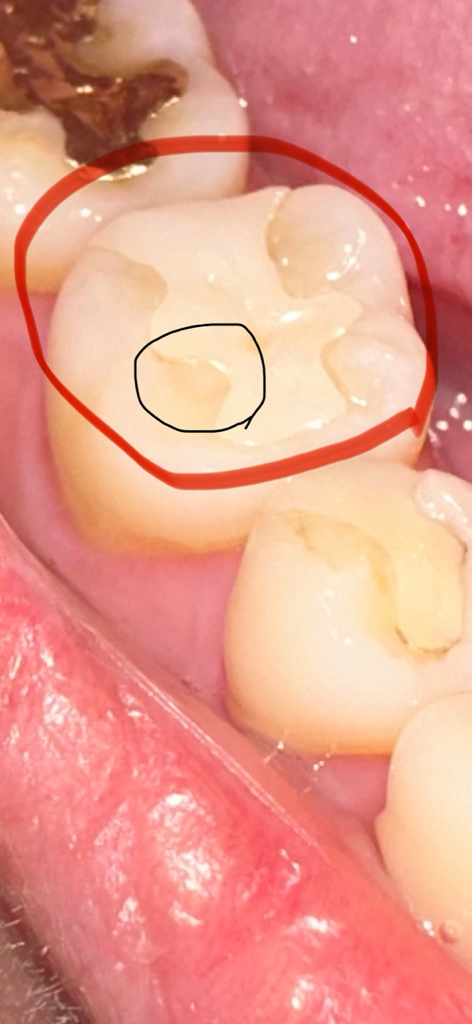

보철물과 치아 사이 틈이 확실히 있는것같은데 틈이 없다고 하시고 전체적으로 다듬어주셨는데 오히려 다른 부분도 더 사이가 벌어진것같은 기분이 들어요.. 저기 밑에 사진 검은부분도 약간 파인것처럼 되었는데 원래 안저렇고 매끄러웠어요 ㅠㅠ 눈으로만 봐도 미세하게 벌어진게 보이는데 왜 다른부분들까지 저렇게 다듬어줘서 파여진 부분도 보이게되고 멀쩡한 부분을 왜 다듬으신건지.. 일반적이라면 교체해야하는게 정상아닌가요 ㅠㅠ 사진도 찍어보자는 말도 안하고.. 이러다 이빨 더 큰 문제되는게 아닐까요..? 위에 사진은 치과 방문 전 이고 밑에 사진이 오늘 다듬은 사진 입니다 전문가분들 도와주세요 ㅠㅠ

• 2번 째 사진